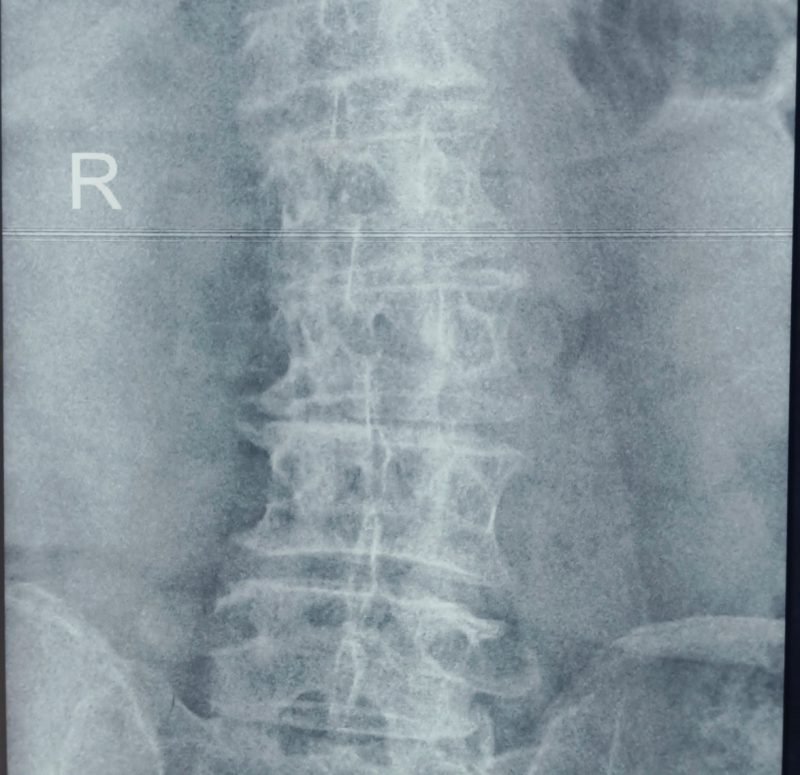

Condition:

An age-related condition where multiple disc degenerations cause the spine to curve to one side.

Symptoms:

Chronic back pain, imbalance, abnormal posture, and reduced mobility.